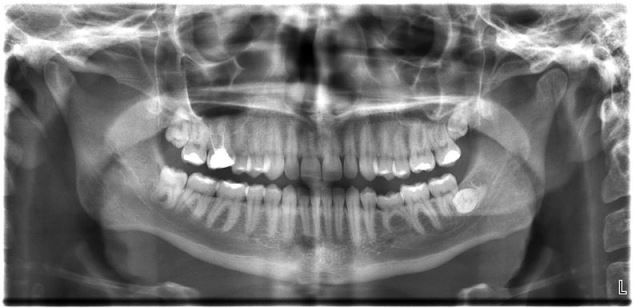

Dental x-rays are an absolutely necessary, indispensable part of diagnostics and analysis. Without it, dentists cannot hope to find the roots of teeth without making the tongue or the face go numb from nerve damage, they would not know where the wisdom teeth that are not entirely erupted are located, and dental implantation would be absolutely impossible, and even basic treatments like root canal treatments would become a hit or miss kind of endeavour, one that doctors are legally liable for. So in order to make sure that you get dental treatment that is good for you and will not cause problems later on, you need to get a dental x-ray.

Reducing the amount of x-rays that touch the person is a great first step in eliminating the carcinogenic nature of this necessary procedure, and dentists have already started doing just that. New and up to date machines emit much less of the cancer causing gamma rays, and soon may be emitting none at all. So when it’s time to get a dental x-ray, don’t be afraid, just know that you cannot get them to frequently.